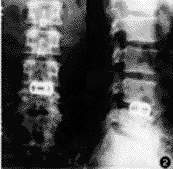

本组7例,4例症状完全消失,1例残留趾端、足背麻木,2例有轻微腰部酸痛感,手术结果均为优良。随访时间12~36个月,X线片示置入假体无一例松动、移位、脱出,无一例复发(图1,2)。

图1 术前腰椎正、侧位X线片,L4-5 椎间隙变窄,L4 棘突和部分椎板缺如